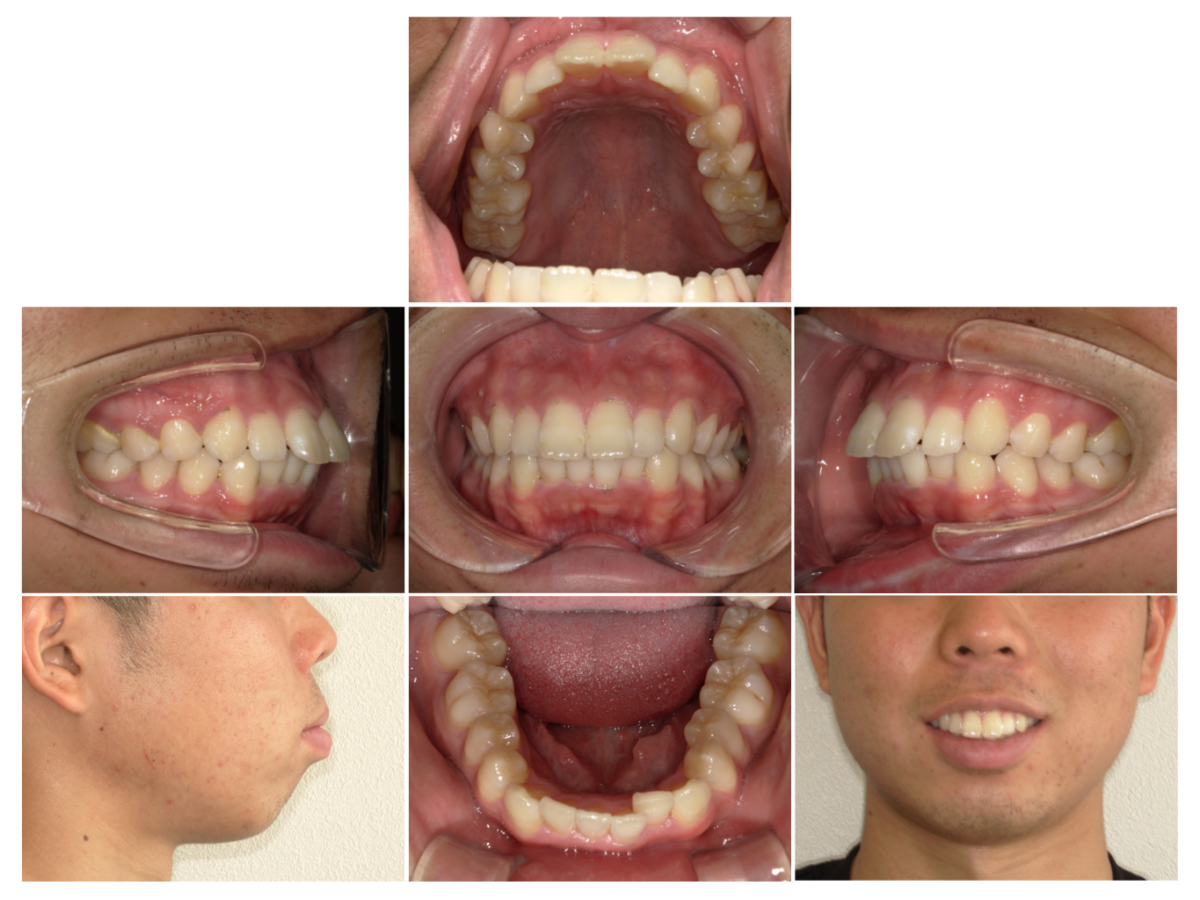

症例2

| 来院時の主訴 | 前歯がガタガタ |

| 医院での対応や適用装置 | マウスピース矯正装置を使用して主訴である叢生の改善を行ないま |

| 通院期間 | 1年3ヶ月 |

| 通院回数 | 9回 |

| 治療費用総額 | 819,500円(税込) |

| リスクと副作用 | 矯正治療による歯の移動に伴う痛み、歯根吸収、虫歯 |